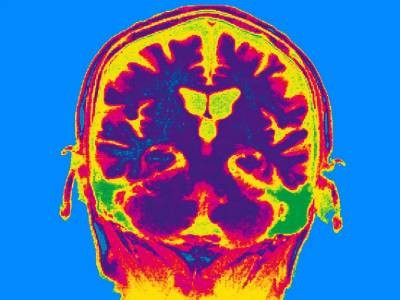

Nagai and his colleagues focused on the question of memory stabilization: how a short-term memory becomes more permanent in the brain. Previous research had found physical traces of memories in neuronal networks in brain regions such as the hippocampus and amygdala2. But it was unclear how these ‘engrams’ were stored in the brain as lasting memories after repeated exposure to the same stimulus.

In a well-established fear-conditioning memory task, mice learnt to associate a certain cage with unpleasant shocks to their feet while the researchers tracked the level of Fos in their brains. Days later, the animals would re-enter the cage and recall the unpleasant sensation. The researchers observed strong Fos upregulation in astrocytes in the animals’ amygdalas and other brain regions when mice re-entered the cage, but not during the initial learning phase, suggesting that astrocyte activity was more important for recalling past events than creating new memories.